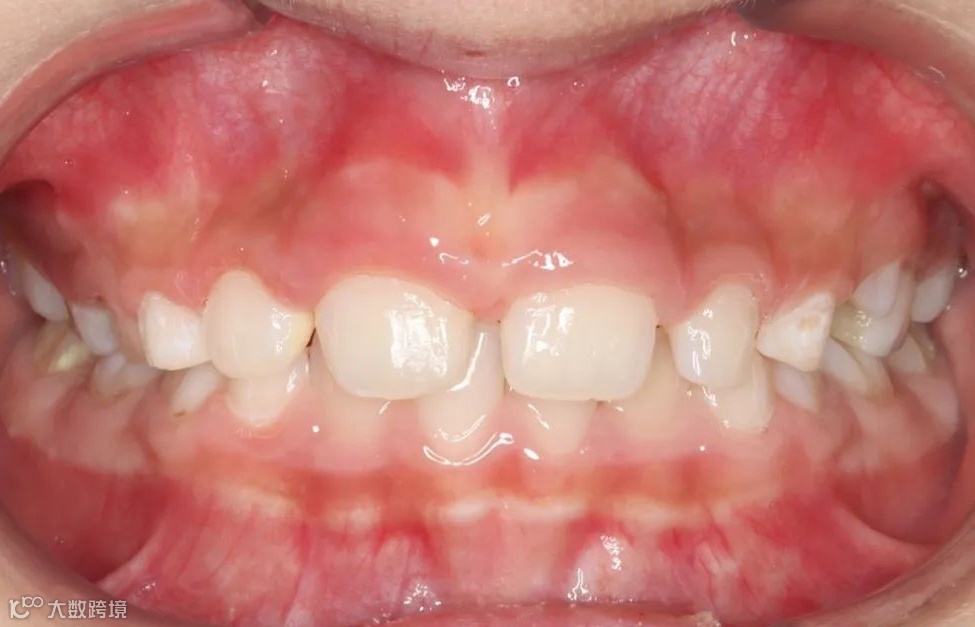

治疗前正面向咬𬌗相

替牙期牙性反𬌗治疗前